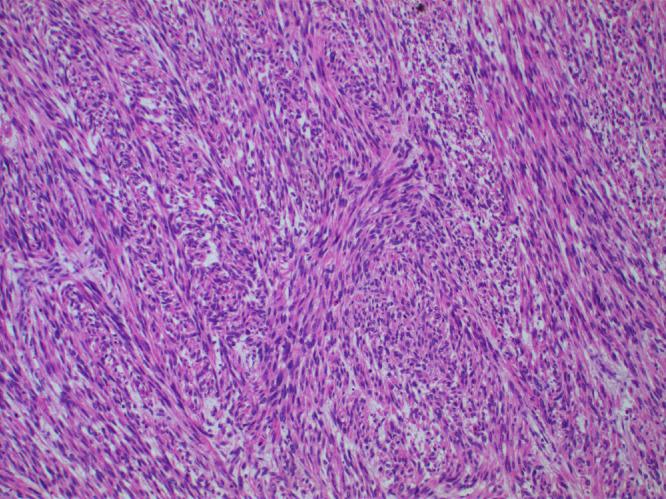

Paratesticular leiomyosarcoma is a rare malignant tumor deriving from the smooth muscle of structures surrounding the testes, including the epididymis or scrotum. With few cases of genitourinary soft tissue sarcomas reported in the literature, little is known about progression, management, and treatment. Herein, we report a case of metastatic paratesticular leiomyosarcoma in a 47-year-old male with no past urological history. The patient initially presented with a firm, painless right scrotal mass, and ultimately developed soft tissue and pulmonary metastases.

睾丸旁平滑肌肉瘤是一种罕见的恶性肿瘤,起源于睾丸周围结构(包括附睾或阴囊)的平滑肌。由于文献中报道的泌尿生殖系统软组织肉瘤病例较少,对于其进展、管理和治疗知之甚少。在此,我们报告一例47岁男性转移性睾丸旁平滑肌肉瘤病例,该患者既往无泌尿系统病史。患者最初表现为右侧阴囊质地坚硬、无痛性肿块,最终出现软组织和肺转移。